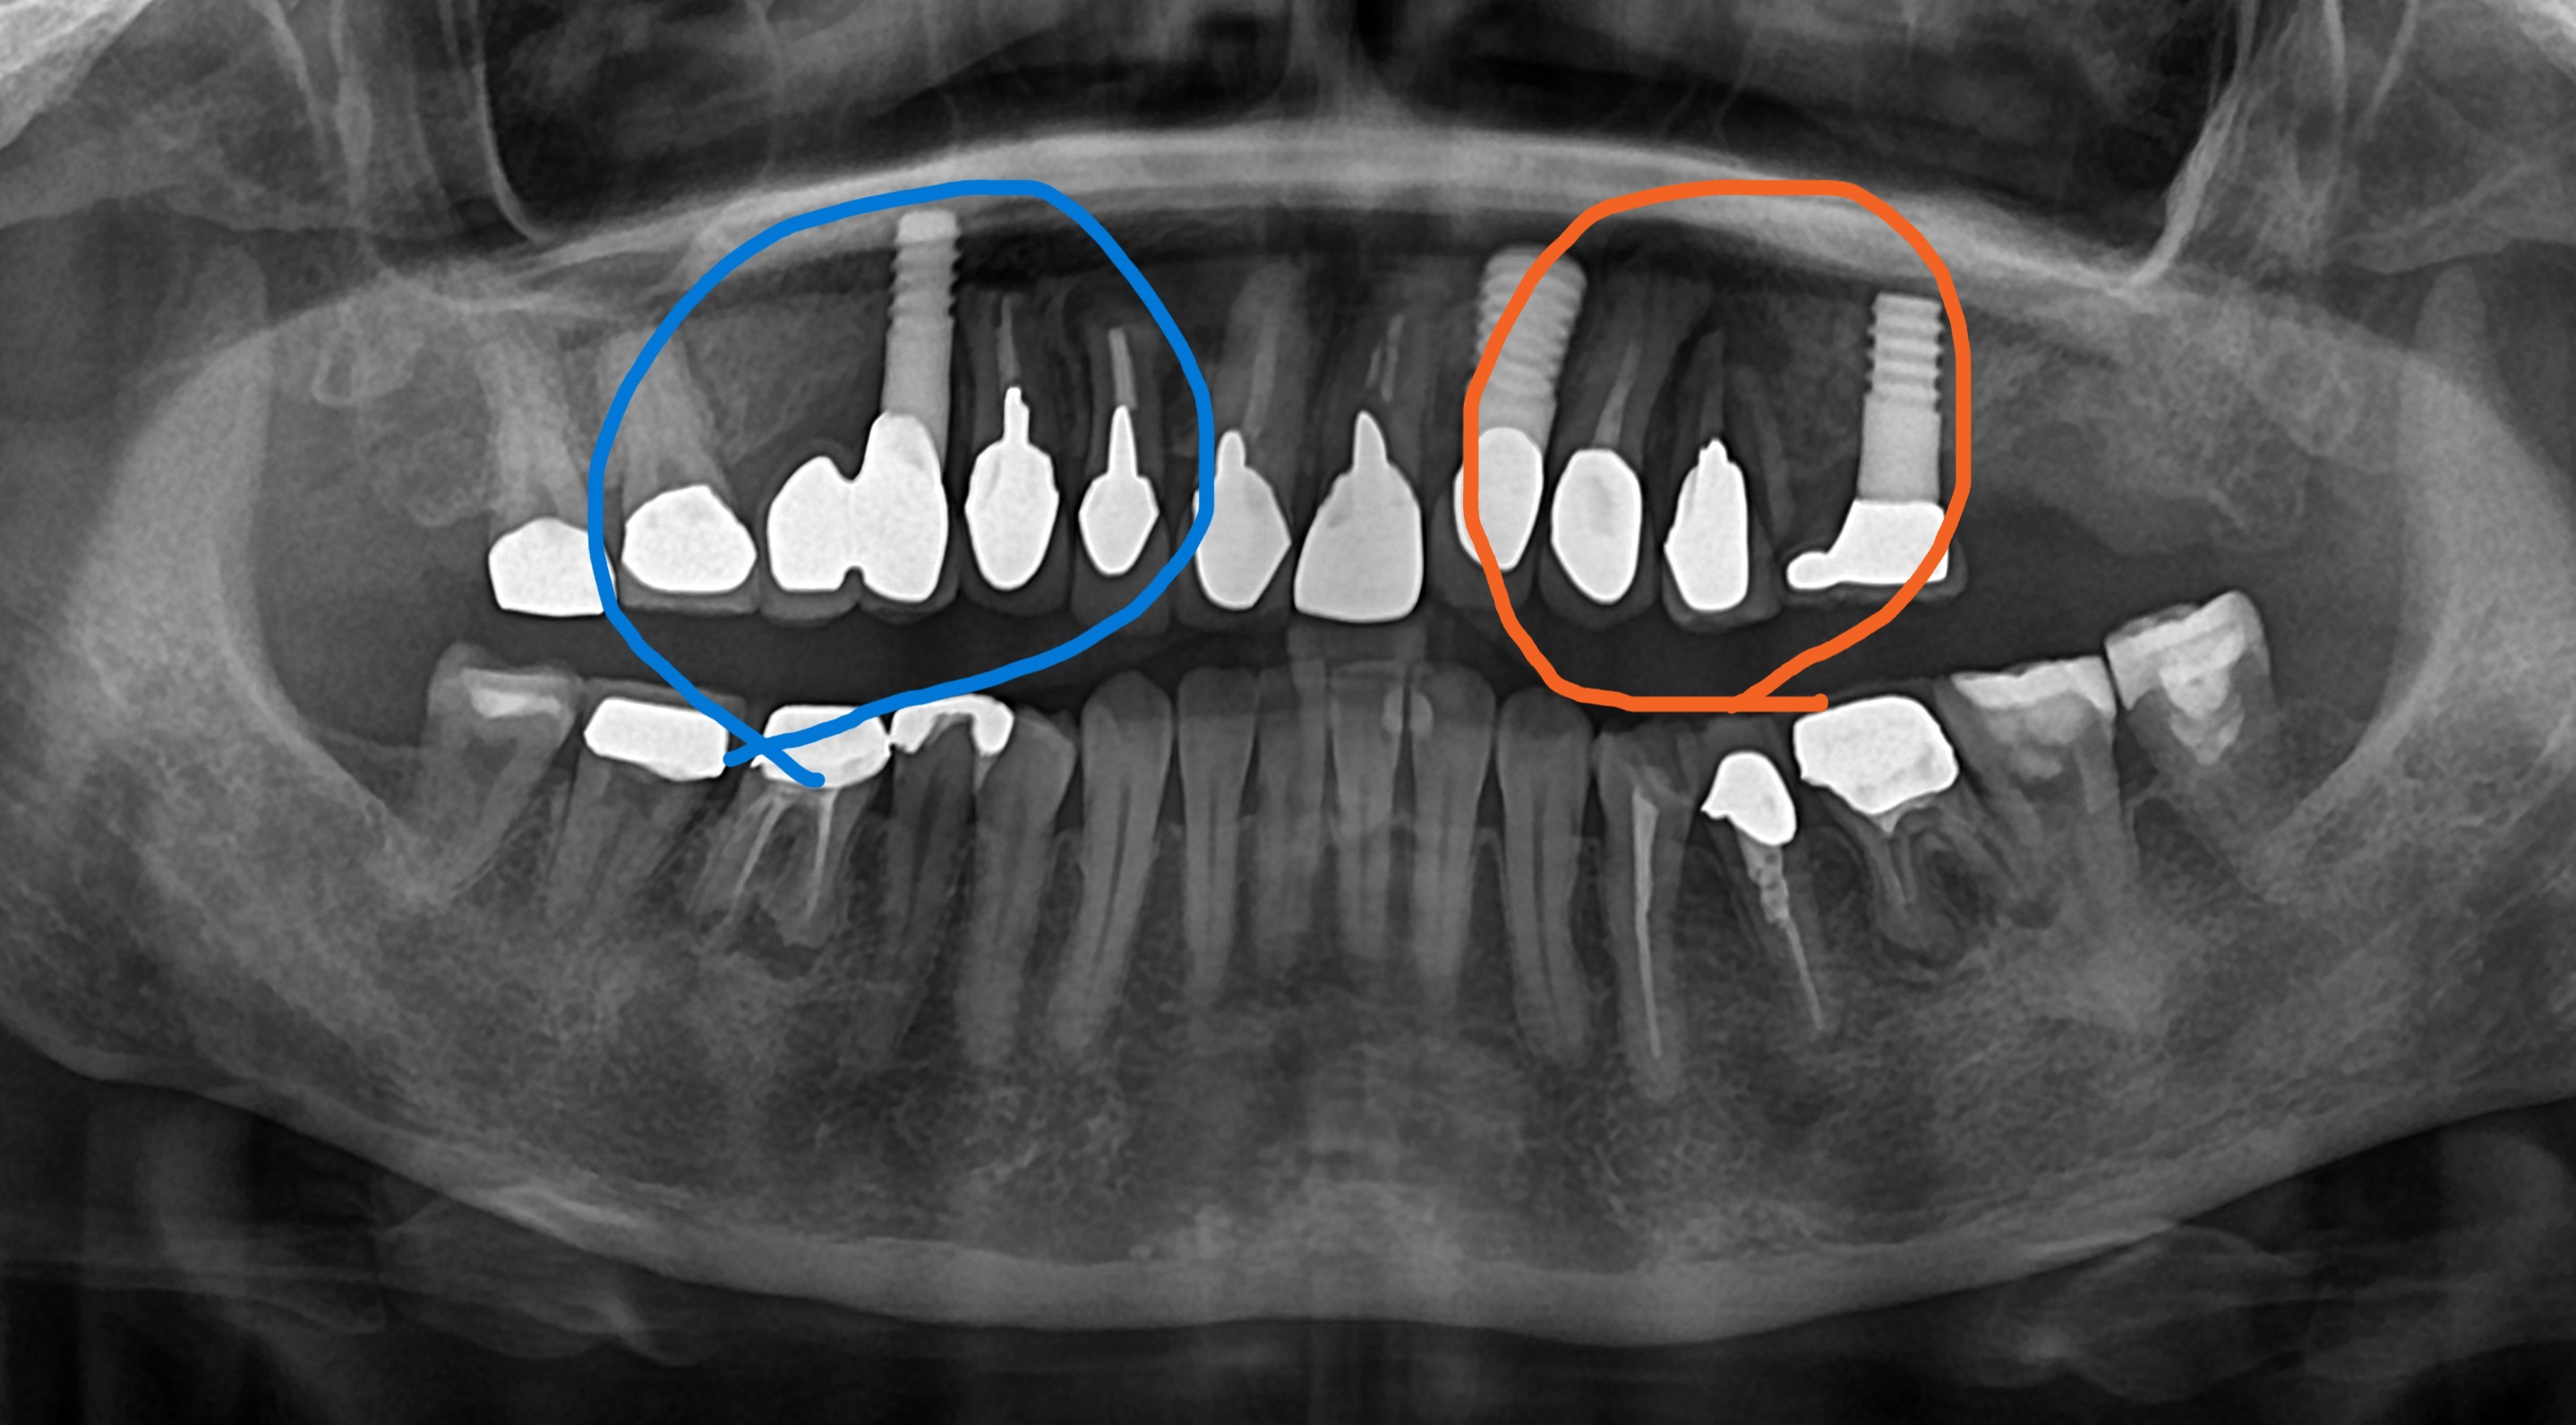

インプラントを長持ちさせるために

先日、ある患者さんの紹介でインプラントを希望する方が来院しました。オレンジ色の線で囲まれている部分の歯が割れているのでその歯を抜いてインプラントを希望していました。患者さんは割れた歯が気になっていたま...